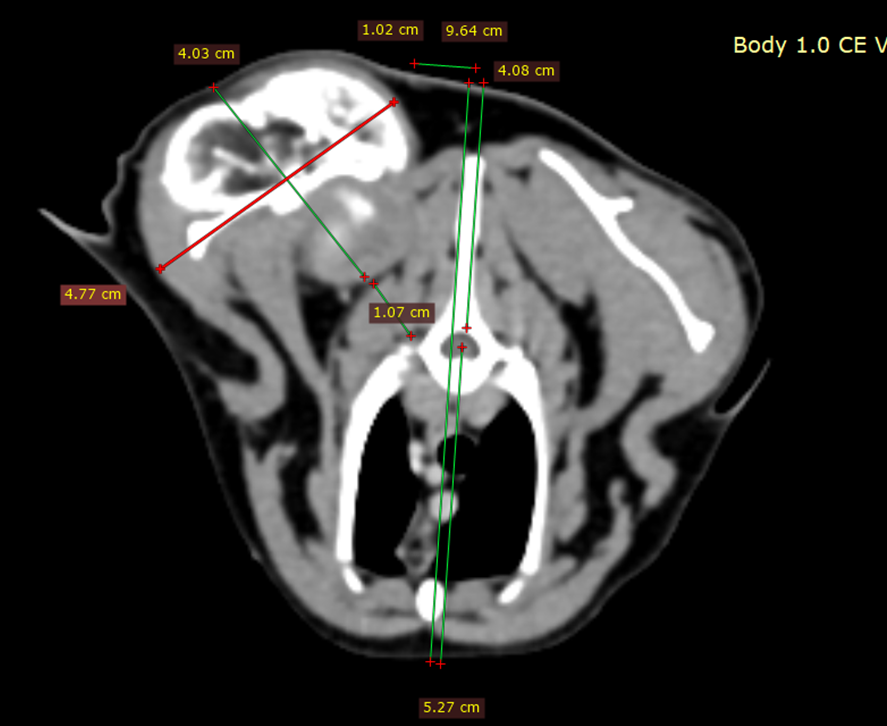

解剖學研究完,我會藉著電腦斷層,更加認識腫瘤本人:

從斷層可以歸納出,

腫瘤分兩塊,一塊黏在肩胛骨上(叫它1號好了),一塊從肩胛骨背側緣延伸出去、呈一顆球狀(2號)。

腫瘤1號,前側就位在肩胛骨infraspinatus fossa,後側剛好切在dorsal border,背側緊貼scapula spine,

腹側只突出肩胛骨caudal border一點點,

底部沒有侵犯超過肩胛骨。

所以可以把1號想像成整個人都長在肩胛骨上,還蠻乖的、沒有往外侵犯太多。

腫瘤2號,整個人壓在脊上肌群上,位置約在第1胸椎到第5胸椎之間,恣意生長,壞壞的感覺,又大顆,是這次手術的頭號敵人,最需要認真剷除的對象。

接著利用電腦斷層的橫切面去一張一張分析:

貓的厚度、胸腔厚度、背到胸腔的距離、腫瘤離胸腔多近…等資訊。

如下圖可得知,

- 整隻貓的厚度: 9.5cm

- 胸腔厚度: 5.5cm

- 背到胸腔的距離: 4cm

- 背中線到腫瘤的距離: 1cm

- 腫瘤底部到胸腔: 1cm

- 腫瘤尺寸: 4.5x4cm

如此一來,就能在腦中對腫瘤與貓貓身體的關係越來越了解。